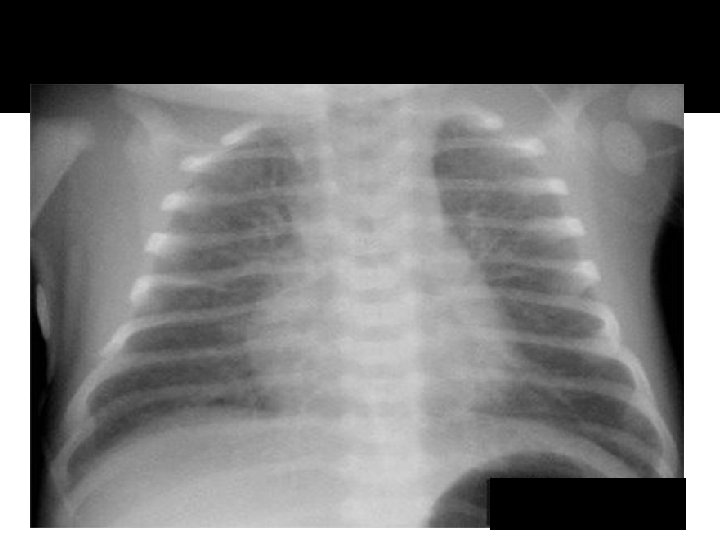

EXAMINATION OF THE RESPIRATORY SYSTEM CHEST: �The symmetry of the chest should be noted, as should any subcostal/intercostal retractions. Asymmetric expansion may be seen with a pneumothorax or diaphragmatic paralysis. Abnormal shapes (e. g. , pectus excavatum or pectus carinatum) should be noted. Barrelshaped chests are sometimes seen in patients with chronic obstructive pulmonary disease (e. g. , chronic asthma or cystic fibrosis).

EXAMINATION OF THE RESPIRATORY SYSTEM LUNGS: �A bell or diaphragm of the appropriate size should be used. Frequently, an adult stethoscope can be used once the child is out of the immediate newborn period. The clarity of the breath sounds and the quality of air movement should be noted.

EXAMINATION OF THE RESPIRATORY SYSTEM �Any wheezing, rhonchi, rales, or transmitted upper airway sounds should be recorded. An increased inspiratory: expiratory ratio is an indication of small airways bronchospasm. Since airway sounds are transmitted better through a smaller chest, the exam can be somewhat confusing at times. Fremitus, whispered pectoriloquy, and percussion are more useful in older children and adolescents than in infants and younger children.

Atelectasis RML

Pneumonia lingula

Atelecasis RML